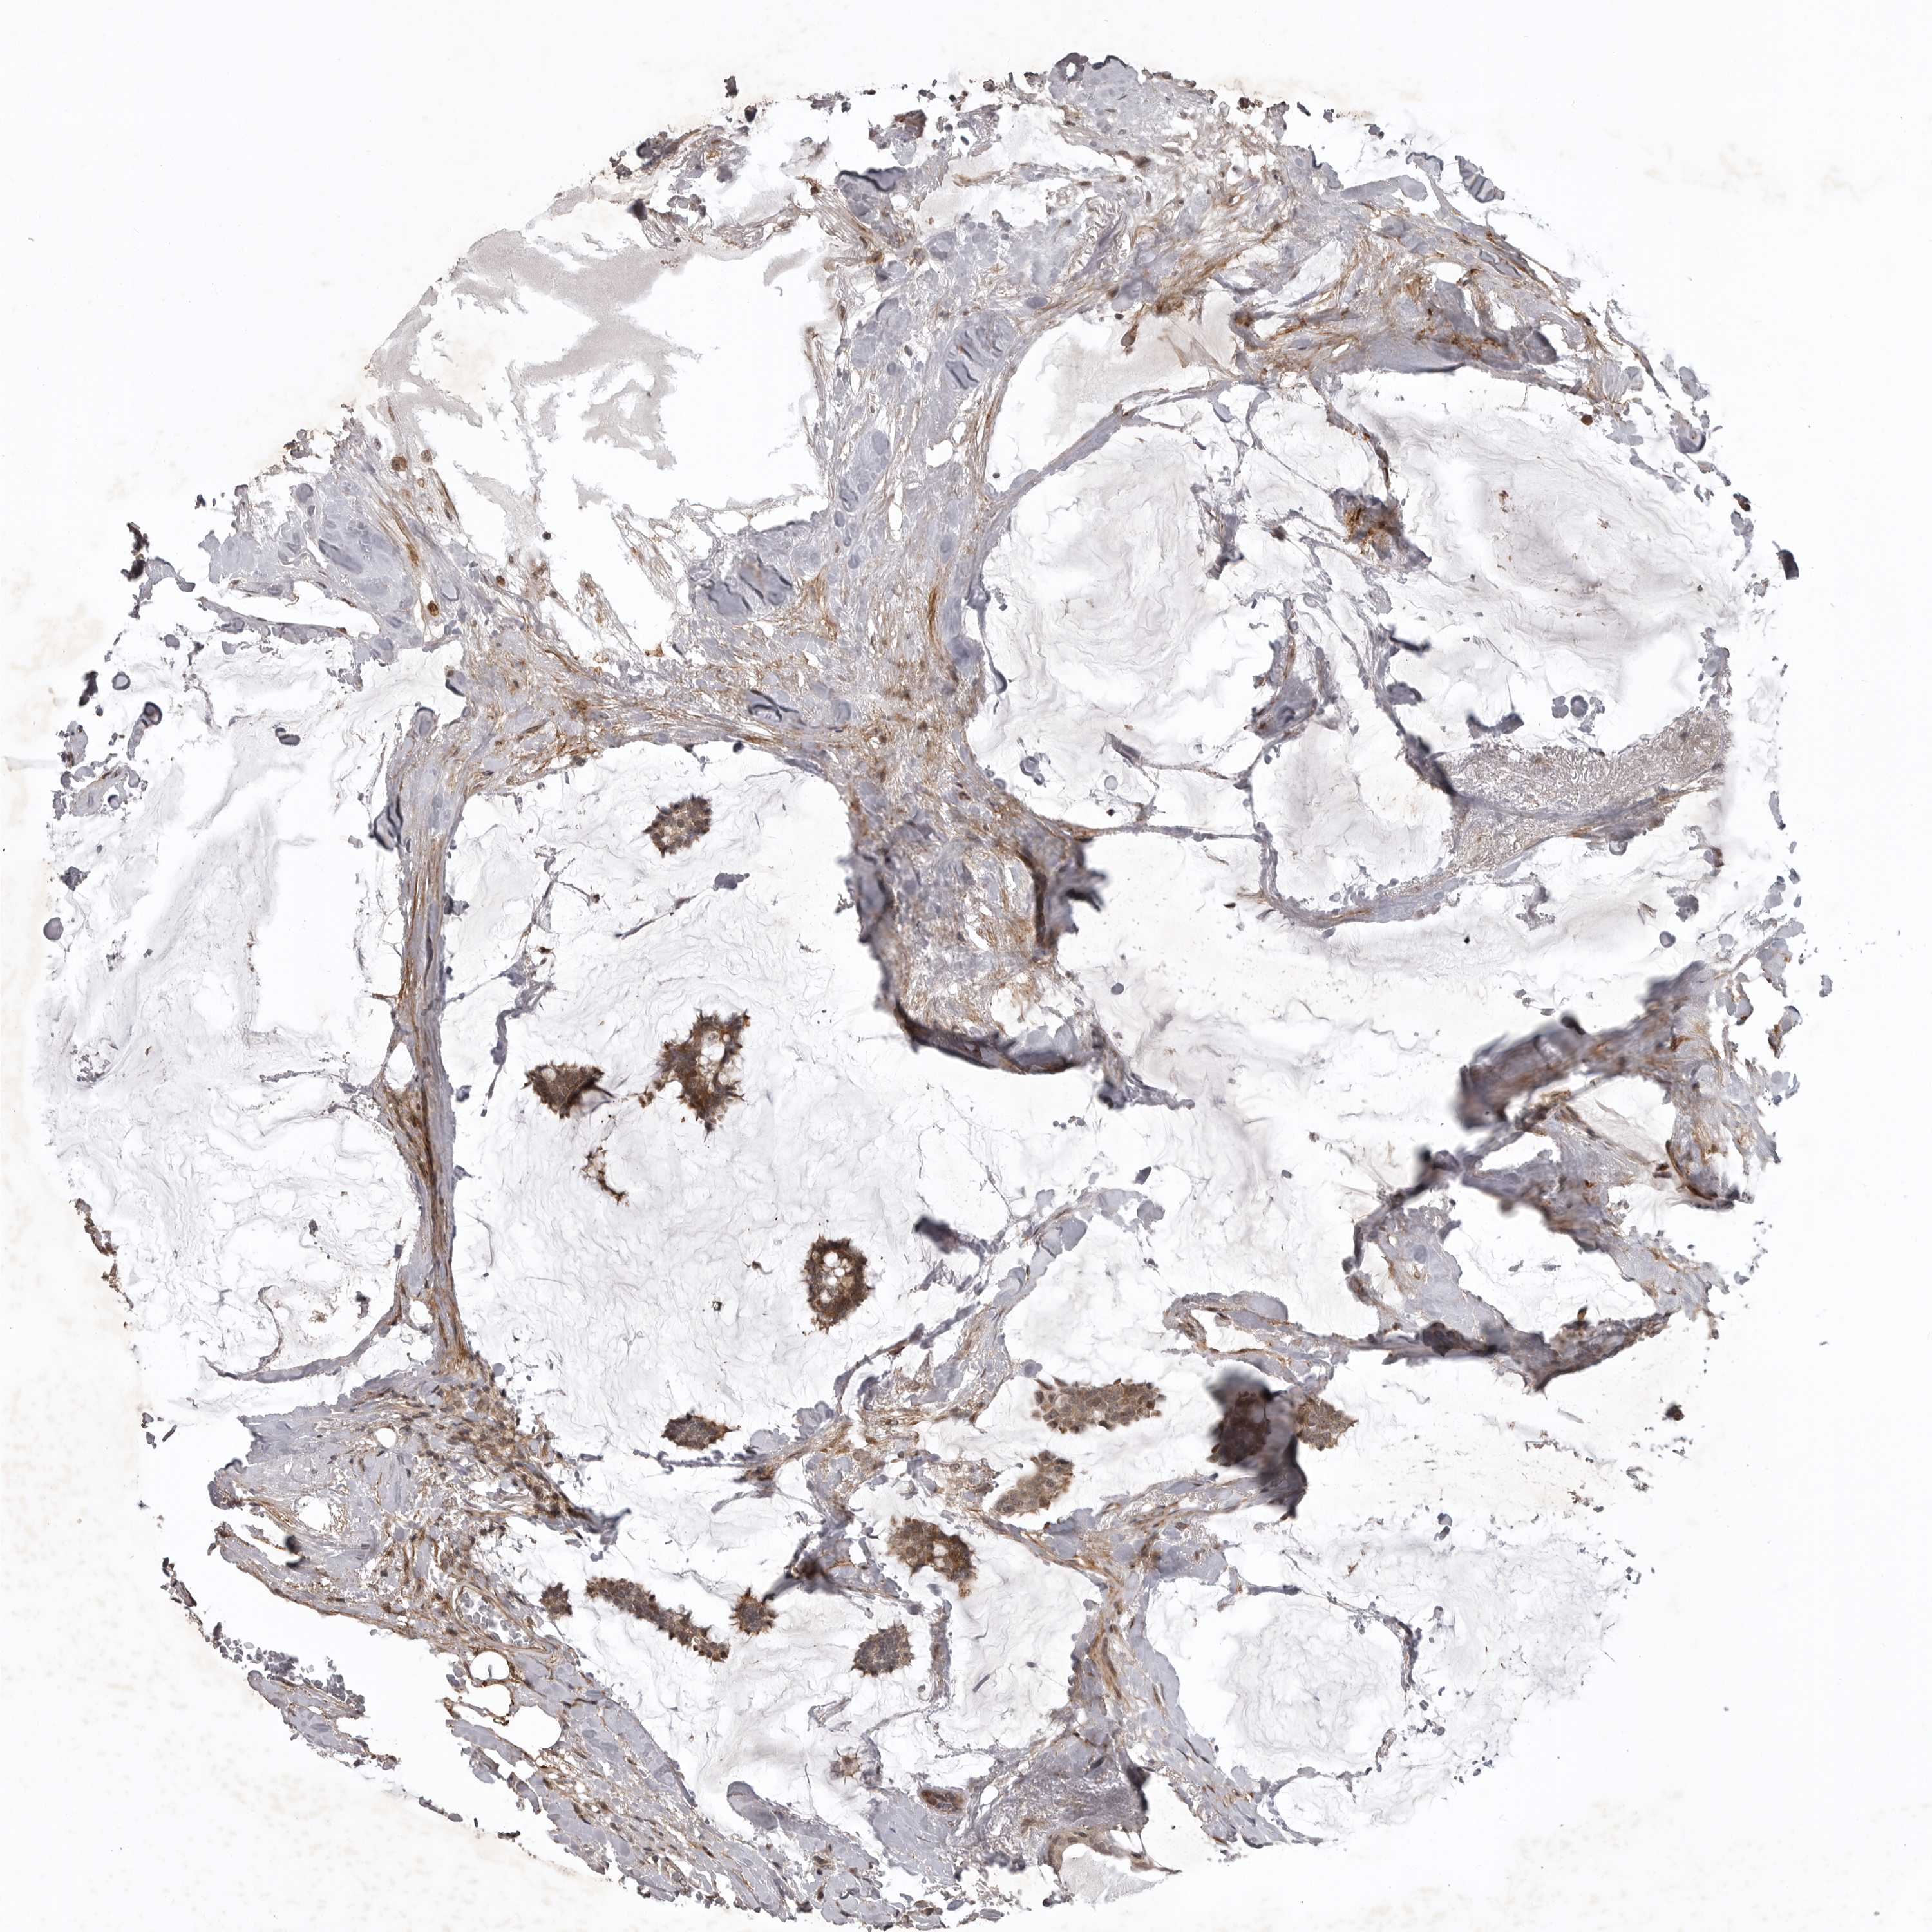

CANCER BREAST CANCER Show tissue menu

BRCA TCGA BRCA VALIDATION PROTEIN EXPRESSION

ANTIBODIES

AND

VALIDATION